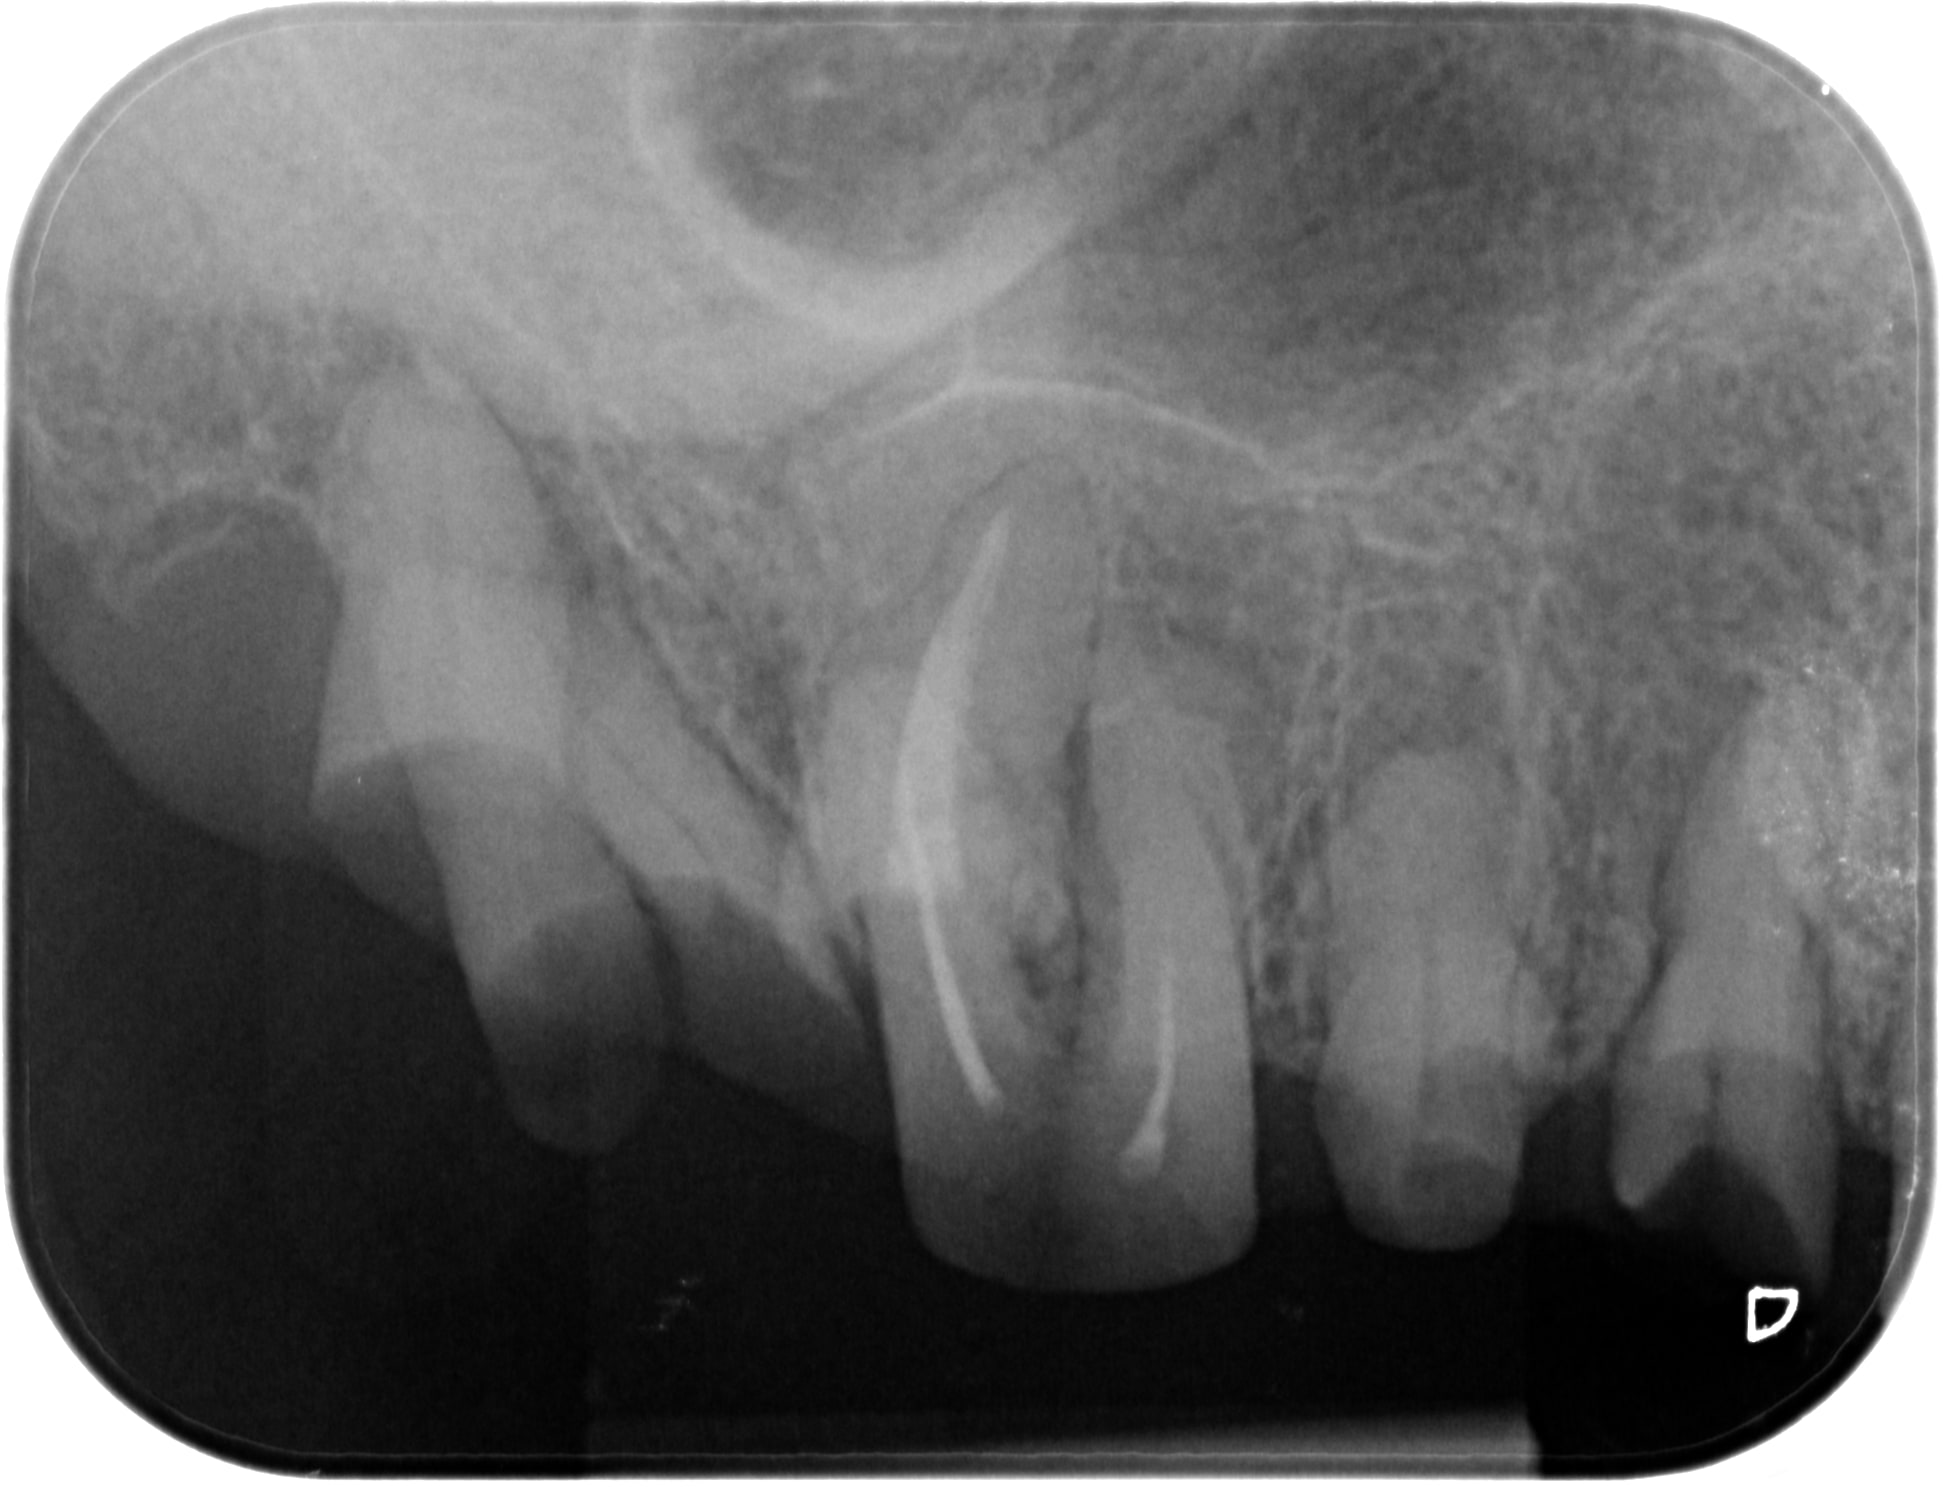

Des comme ça j'en 2 ou 3 par semaine (vu à l'instant ) ... Petite question : quel âge à ce patient ? Deuxième question à Carident et à quelques autres, quel est le montant de votre plan de traitement ? ( je ne demande pas le détail )(@ lardon , la 15 en métal , marqueur social ? ) .. troisième question : pensez vous que ce patient a la mutuelle adéquate à son état dentaire et enfin : pensez-vous que ce patient serait mieux pris en charge grâce au RAC 0 ? On va faire dans le concret de pas mal de cabinet dentaire ....

Pour l'age, c'est pas pour l'expulser, mais c'est impossible à dire par rapport à la radio. Au delà de 18 ans, c'est certain, tu ne sera pas arrêté pour détournement de mineur.

Puisque tu en parles, ca doit être la trentaine. Il a eut différentes extractions réalisées au cour du temps et à abandonné déjà les soins en cours de route.

C'est bien pour cela que c'est impossible de parler de devis et de tarifs, puisque quelque soit le devis, les probabilités d'arriver au bout du plan de traitement sont faible et il abandonnera bien avant les prothèses sur des soins opposables ce qui montre que le tarif et les remboursements ne sont pas en cause.

Age 19 Ans ! , et bien sûr qu'il ira au bout du traitement s' il peut financièrement ! Il est motivé , c'est un jeune homme "bien" . sérieux , il est à l'heure , n'est pas peureux .. bref , ce genre de patient où tu sais pertinemment que ce qui va coincer c'est l'argent . Barba , il existe des patients non serieux à tous les niveaux de la société et quand c'est un cadre , là , on pense qu'il n'a pas le temps . Alors , on fait quoi pour ce jeune , on le prend en charge ( nous la société ...) ? on lui dit que c'est trop tard ? t'avais qu'à te brosser les dents ? ( vous avez remarqué qu'il a eu déjà de nombreux soins ) . Et, s'il vous plait, gardez pour vous vos généralisations à 2 balles ! ( barba , tu me suis ? ) . Ah ouais aussi , je ne lui ai pas mis un devis sous le nez avant de commencer à le soigner .. évidemment !

Je précise aussi , ce patient n'est pas venu parce qu'il avait mal .... étrange , non ?